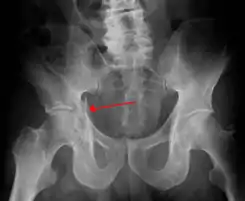

![]() Radiografía en la que puede visualizarse una fractura de acetábulo | ||